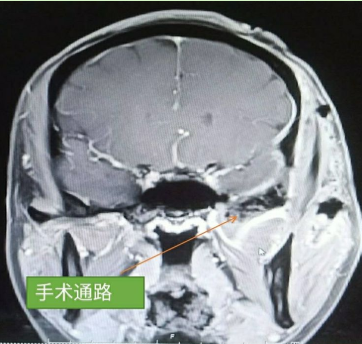

颅脑核磁示:左侧颞下窝占位。

术前核磁

术前增强MRI

结合术前颞骨CT薄层扫描+增强核磁,我们应该选择入路?

内镜侧颅底入路?

硬膜下入路?

硬膜外入路?